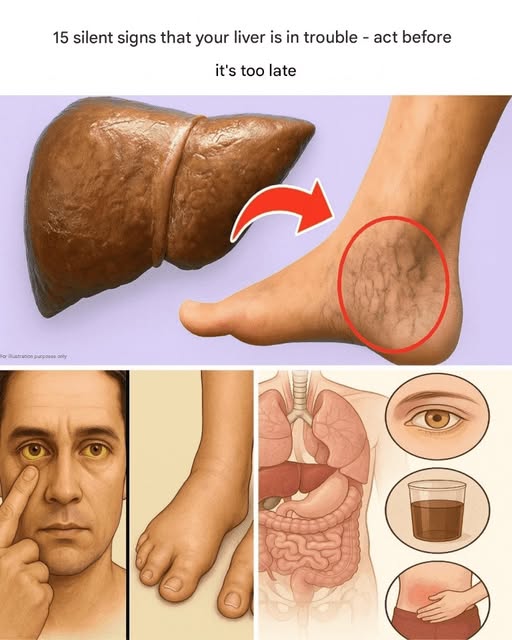

Your liver is a silent hero, working tirelessly to detoxify your body, regulate hormones, balance blood sugar, and support digestion. But when it’s under stress, it doesn’t always send out loud signals. Instead, it gives off subtle signs that something is wrong—signs that can be easily dismissed or overlooked.

Ignoring these early symptoms can lead to serious conditions like fatty liver disease, hepatitis, or even cirrhosis. The good news? Your liver is incredibly resilient and can recover—if you recognize the warning signs early and take action.

Here are 15 subtle but serious signs that your liver may be in trouble:

For illustrative purposes only